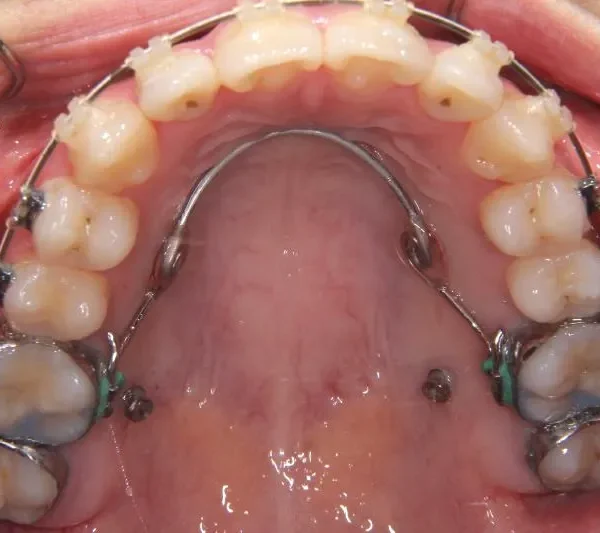

• 治療経過1

治療経過1

マルチブラケット装置

歯科矯正用アンカースクリュー

歯科矯正アンカースクリューを用いた治療で、非抜歯で口唇突出の改善、臼歯の圧下、叢生の解消を図りました。